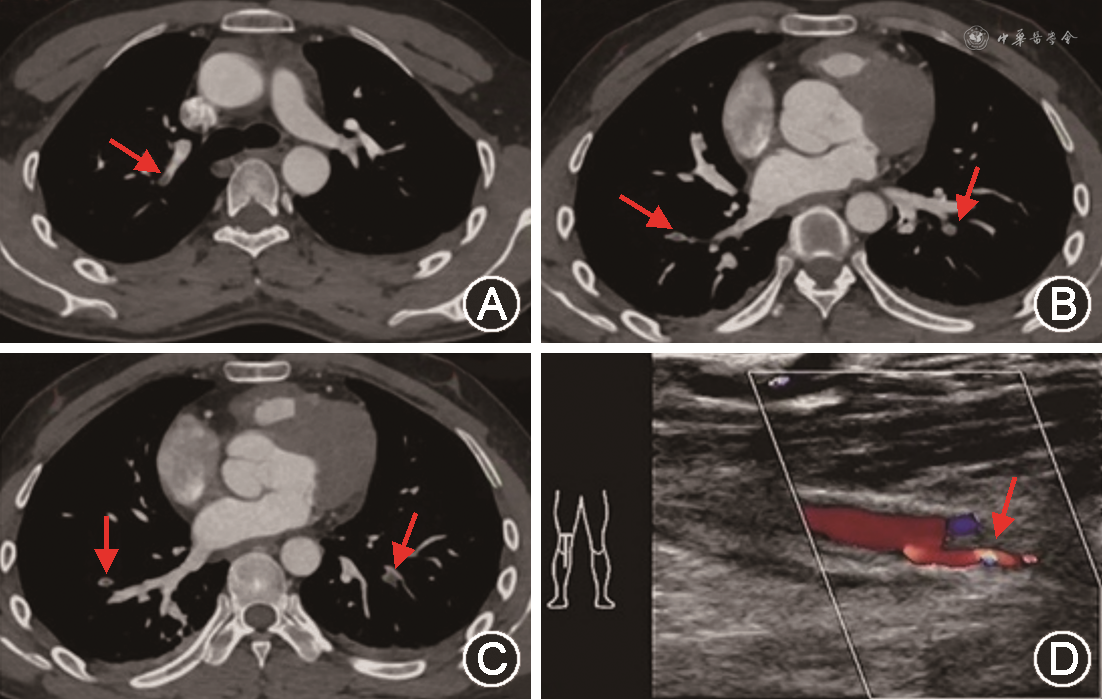

临床资料 患者男性,26岁。2020年1月5日因“突发言语含混、右侧肢体无力2周”收入我科,不伴头痛、发热、肢体抽搐、意识障碍,外院头颅MRI示左侧额颞顶枕叶、岛叶及基底节区大片状异常信号灶并部分强化,疑感染性病变,于外院治疗后症状无缓解转诊我院。既往否认高血压、糖尿病史;吸烟史10年,每日10支,否认饮酒史,否认脑血管病家族史。入院体检:肥胖体型,体重指数31 kg/m2,体温36.7 ℃,脉搏70次/min,呼吸20次/min,血压146/90 mmHg(1 mmHg=0.133 kPa)。意识清楚,构音障碍,反应迟钝,理解力下降,部分指令不能完成,右侧中枢性面舌瘫,右侧肢体肌张力增高,右上肢肌力0级、右下肢肌力2级,右侧腱反射(++++),右侧偏身针刺觉减退,右侧上下肢病理征阳性,左肢肌力、肌张力、腱反射正常,未引出病理征。入院后监测血压均在正常范围。辅助检查:2019年12月25日于外院行颅脑MRI平扫+增强示左侧额颞顶枕叶、岛叶及基底节区大片状异常信号灶并部分强化,疑感染性病变(图1A~D)。2020年1月6日我院颅脑MRI平扫+DWI+灌注加权成像考虑左侧额颞顶枕叶、岛叶及基底节区脑梗死恢复期;灌注扫描示左侧大脑半球灌注减低(图1E~K)。2020年1月6日行头颈CTA检查示左侧大脑中动脉M2段分支显示不清、其远端分支稀疏(图1L);冠状动脉CT成像未见明显异常;扫及左下肺静脉充盈缺损影。1月6日查右侧上下肢血管彩超示右侧上下肢动脉、静脉血流通畅。2020年1月10日进一步完善左心房-肺静脉CT成像显示右上肺及双下肺肺动脉部分分支内肺动脉栓塞(图2A~C),左心房未见明显血栓形成征象。患者病程中无胸闷、呼吸困难、胸痛、咳血等表现,监测经皮血氧饱和度大于95%。1月13日复查四肢动静脉彩超发现右下肢腘动脉、胫前动脉血栓形成(图2D);四肢深静脉血流通畅。右下肢体检见足背动脉未扪及,右足皮温较左侧稍降低,无明显皮肤青紫、足趾坏死等。心电图示窦性心律。心脏超声未见明显异常。血Hcy 416.25 μmol/L(正常范围0~15.00),血叶酸、维生素B12水平正常,凝血功能及D-二聚体水平均正常。血常规:白细胞计数12.72×109/L(正常值:3.50×109/L~9.50×109/L),血小板369.0×109/L(正常值:125.0×109/L~350.0×109/L);血脂:甘油三酯 2.68 mmol/L(正常值<1.70 mmol/L),低密度脂蛋白胆固醇 3.59 mmol/L(正常值<3.37 mmol/L);C反应蛋白27.76 mg/L(正常值:0~5.00 mg/L),白细胞介素-6 56.63 pg/ml(正常值:0~7.00 pg/ml);尿酸 498 μmol/L(正常值:210~420 μmol/L),丙氨酸氨基转移酶 100 U/L(正常值:9~50 U/L);红细胞沉降率 60 mm/h(正常值:0~15 mm/h);抗“O”、类风湿抗体均未见异常;自身抗体检查示:抗增殖细胞核抗原抗体呈弱阳性,余均为阴性。结核感染T细胞斑点试验、结核抗体为阴性。2020年1月19日完善患者的基因检测,结果提示CBS基因发生变异,通过对其父母及弟弟进行基因验证,发现患者CBS为复合杂合变异,2个突变基因分别来源于其父亲和母亲(图3)。其父亲血Hcy浓度19.71 μmol/L,母亲血Hcy浓度9.33 μmol/L,患者父母的叶酸、维生素B12水平及凝血功能均正常。患者诊断为急性脑梗死,TOAST分型考虑其他原因型,予低分子肝素序贯利伐沙班抗凝,补充叶酸、维生素B6、甲钴胺,同时予降脂、改善循环、营养神经等治疗,1周后复查患者Hcy水平下降至169.29 μmol/L,2周后复查Hcy降至79.88 μmol/L,结合康复治疗、针灸治疗,2020年1月22日患者出院时能间断说出个别简单词汇,右侧上肢近端肌力Ⅰ级,远端肌力0级,右下肢肌力Ⅲ级,未见新发血栓。出院后继续予抗凝、调脂稳斑、叶酸、甲钴胺、维生素B6口服等降同型半胱氨酸治疗,1年后随诊未见新发血栓形成,复查Hcy水平为12.50 μmol/L。

血管并发症是HCU发病和早死的主要原因,不同基因型HCU患者血栓事件发病率差异很大,可以影响任何血管,包括静脉血栓和动脉血栓,其中静脉血栓更常见。根据目前报道的大量病例系列,未经治疗的HCU患者血栓事件50%为深静脉血栓形成(其中1/4与肺栓塞有关),脑卒中(包括脑静脉窦血栓形成)占血管并发症的32%,外周动脉疾病占11%,心肌梗死仅占4%[8]。目前尚无研究统计c.833T>C点突变HCU患者血栓事件的患病率,脑梗死合并肺栓塞及下肢动脉血栓形成也罕见报道。针对HCU的长期管理,降低血Hcy浓度是降低血栓风险最重要的措施。2017年国际CBS缺乏症诊断及管理指南推荐,对维生素B6有反应的患者,血浆总Hcy的目标应小于50 μmol/L,而对维生素B6无反应的患者,建议血浆总Hcy水平保持在100 μmol/L以下,具体措施包括低蛋氨酸饮食、补充维生素B6、叶酸、维生素B12及应用甜菜碱治疗[8]。HHcy导致缺血性脑卒中的病理机制包括动脉粥样硬化性血栓形成和血栓栓塞两个方面,因此对于合并脑动脉血栓的HCU患者,需要给予抗凝和(或)抗血小板治疗进行血栓的二级预防。由于HCU属于罕见疾病,HCU并发脑动脉血栓的研究仅见于个案报道,目前尚缺乏大样本量的临床研究比较抗凝和抗血小板的治疗效果。在临床实践中,需根据患者动脉粥样硬化狭窄的程度、血小板的数目及功能、血流动力学以及凝血功能状态综合分析患者脑动脉血栓的病理机制。本例脑梗死患者合并肺动脉栓塞以及下肢动脉血栓,而下肢深静脉未见血栓,说明患者血栓形成与卧床、血流缓慢关系不大,肺动脉血栓并非来源于下肢深静脉以及心脏,而是肺动脉自身血栓栓塞,考虑高Hcy血液高凝状态导致患者易栓症。结合患者头颈部CTA提示左侧大脑中动脉M2段分支显示不清、其远端分支稀疏,未见脑动脉粥样硬化征象,故考虑患者脑梗死的机制很可能与肺动脉栓塞机制类似,TOAST分型考虑其他有明确原因的脑梗死,具体梗死机制考虑CBS c.833T>C/1082C>T复合杂合变异型高Hcy所致脑动脉血栓栓塞。此类患者建议长期抗凝预防血栓事件再发,动态随访复查左侧大脑中动脉血管病变,若出现明显动脉粥样硬化狭窄表现,要考虑抗血小板聚集治疗。